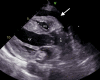

Rare Presentation of Cardiac Tamponade in a Patient With Subclinical Hypothyroidism

Cardiovascular effects of hypothyroidism include bradycardia, diastolic hypertension, atrial fibrillation, prolonged QT interval leading to torsades de pointes, varying degrees of AV block, accelerated coronary artery disease, and pericardial effusion. Cardiac tamponade is rare in patients with hypothyroidism because of pericardial distensibility and slow accumulation of fluid. The amount and rate of accumulation of pericardial effusion are related to the severity of hypothyroidism. Though rare, significant pericardial effusion can be a manifestation of subclinical hypothyroidism.